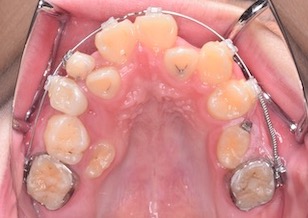

BeforeⅢは、右上顎第2大臼歯が萌出開始しています。左上の乳歯が脱落し、左上顎第2小臼歯にマルチブラケット装置を装着して牽引中のお写真です。